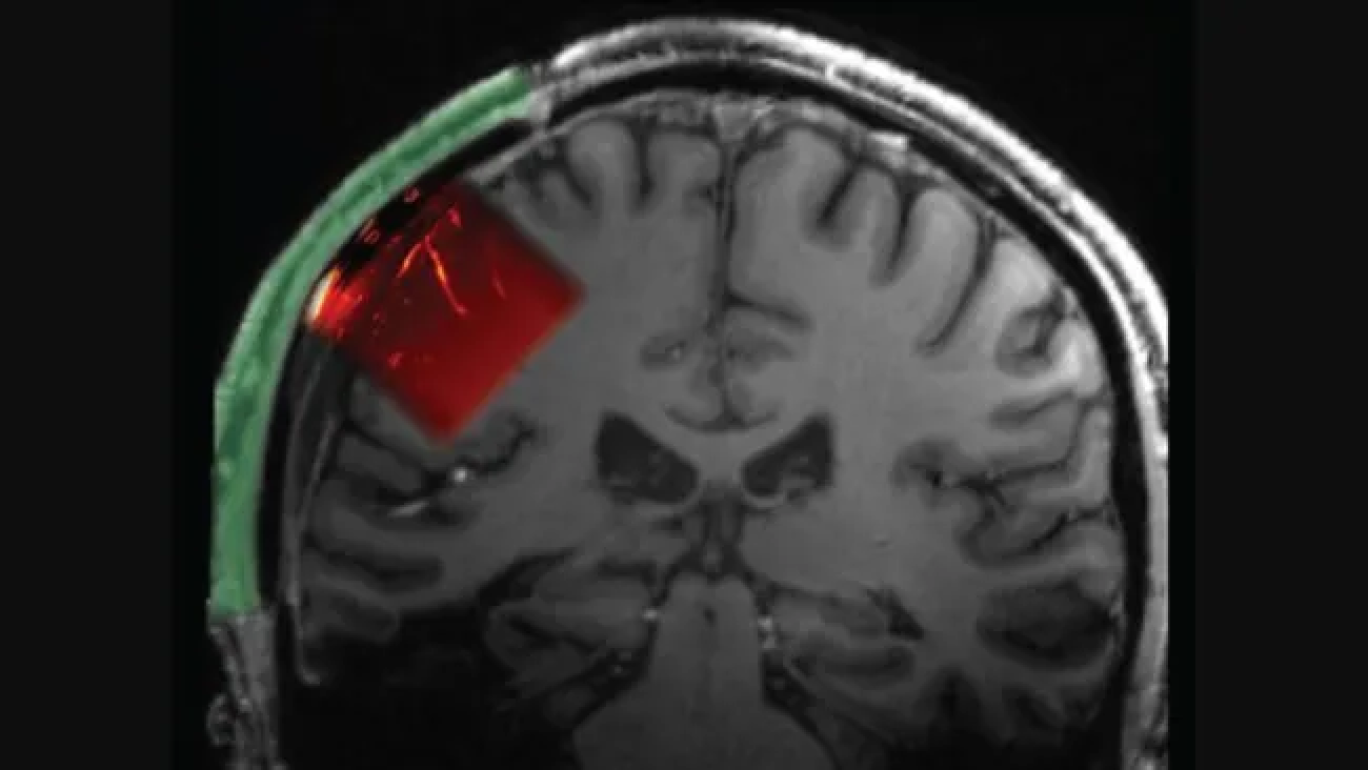

به گزارش لایوساینس، محققان ایمپلنتی را در جمجمه این مرد کاشتهاند که به امواج فراصوت اجازه عبور میداد. این امواج پس از ورود به مغز از این پنجره «شفاف صوتی» (آکوستیک)، از مرزهای بین بافتها رد شدند. سپس برخی از این موجهای بازتابیافته به کاوشگر فراصوت که به یک اسکنر متصل بود بازگشتند. این دادهها به دانشمندان امکان داد از آنچه در مغز این مرد میگذشت، تصویری تولید کنند؛ شبیه به آنچه هنگام سونوگرافی جنین در شکم مادر انجام میشود.

جمجمه انسان همواره مانعی در برابر امواج فراصوت بوده و از ورود آنها به مغز جلوگیری میکرده است. به همین دلیل تیم تحقیقاتی این روش را روی بیماری آزمایش کرد که برای کاهش فشار مغزش پس از یک آسیب شدید، بخشی از جمجمهاش را برداشته بودند و برای او یک ایمپلنت شفاف صوتی ساخت؛ آنچه ممکن است در آینده به بیماران دچار آسیبمغزی محدود نباشد.